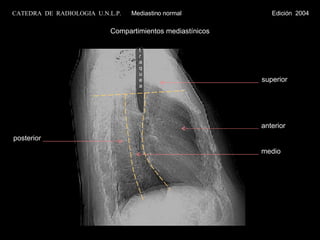

Compartimientos mediastínicos traquea CATEDRA  DE  RADIOLOGIA  U.N.L.P.   Mediastino normal  Edición  2004 anterior medio superior posterior

Compartimientos mediastínicos traqueaCATEDRA DE RADIOLOGIA U.N.L.P. Mediastino normal Edición 2004 anterior medio superior posterior